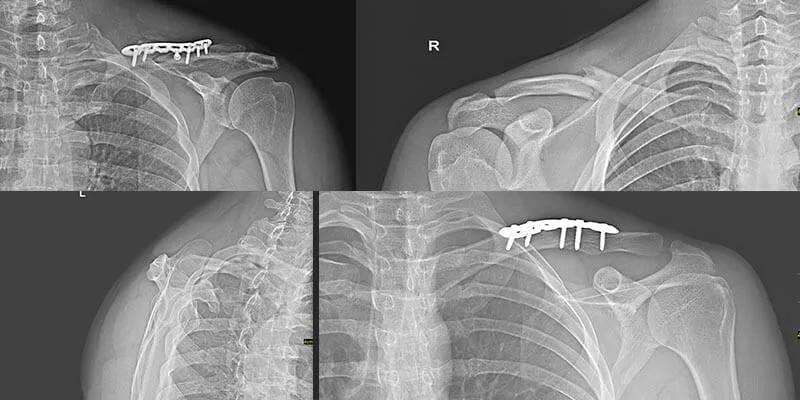

Rehabilitacja po złamaniach obojczyka z przemieszczeniem, które często wymagają operacji, jest bardziej złożona i czasochłonna. Po operacji, która może obejmować użycie płytek i śrub, pacjent zazwyczaj może rozpocząć ruchy ramieniem już po kilku dniach. Czas rehabilitacji w takich przypadkach wynosi zazwyczaj od 6 do 12 miesięcy, w zależności od stopnia uszkodzenia oraz indywidualnych możliwości pacjenta. W pierwszych tygodniach po operacji rehabilitacja koncentruje się na delikatnych ruchach, które mają na celu zapobieganie sztywności stawu oraz przywracanie podstawowej funkcji kończyny.